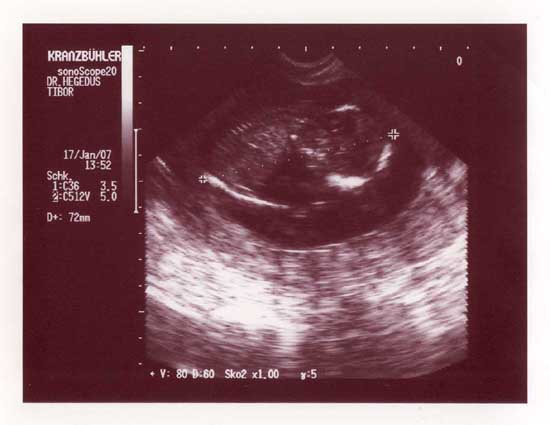

felteszem a mai fotót a babácskáról.

:lol: Kép babácska

Teljesen jó a nagysága a babádnak! Mi tegnap voltunk dokibácsinál, volt UH és 14+2 naposan 72mm-es a CRL. Szal szépen fejlődik, fejlődnek :lol:

Úgyhogy nyugi Szilvi bébi, minden a legnagyobb rendben van!!

Amúgy feljebb láthatsz a babánkról képecskét..